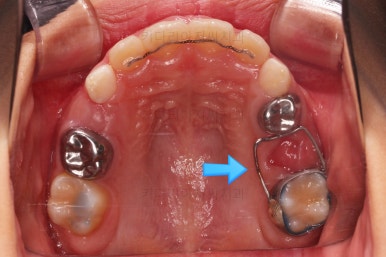

치료가 도저히 불가능한 유치는 발치를 하고, 대신 영구치가 나오기까지 매우 오래 걸릴 것으로 예상되어서 주위 치아들의 위치가 잘 유지되라고 공간유지장치를 해줬어요.

전문 용어로 band&loop라고 하는 이렇게 해줘야 추후에 또 다른 더 큰 문제가 생기지 않는답니다.

제 시기보다 한참이나 먼저 빠진 유치는 치아 공간유지장치를 꼭 염두에 두세요.